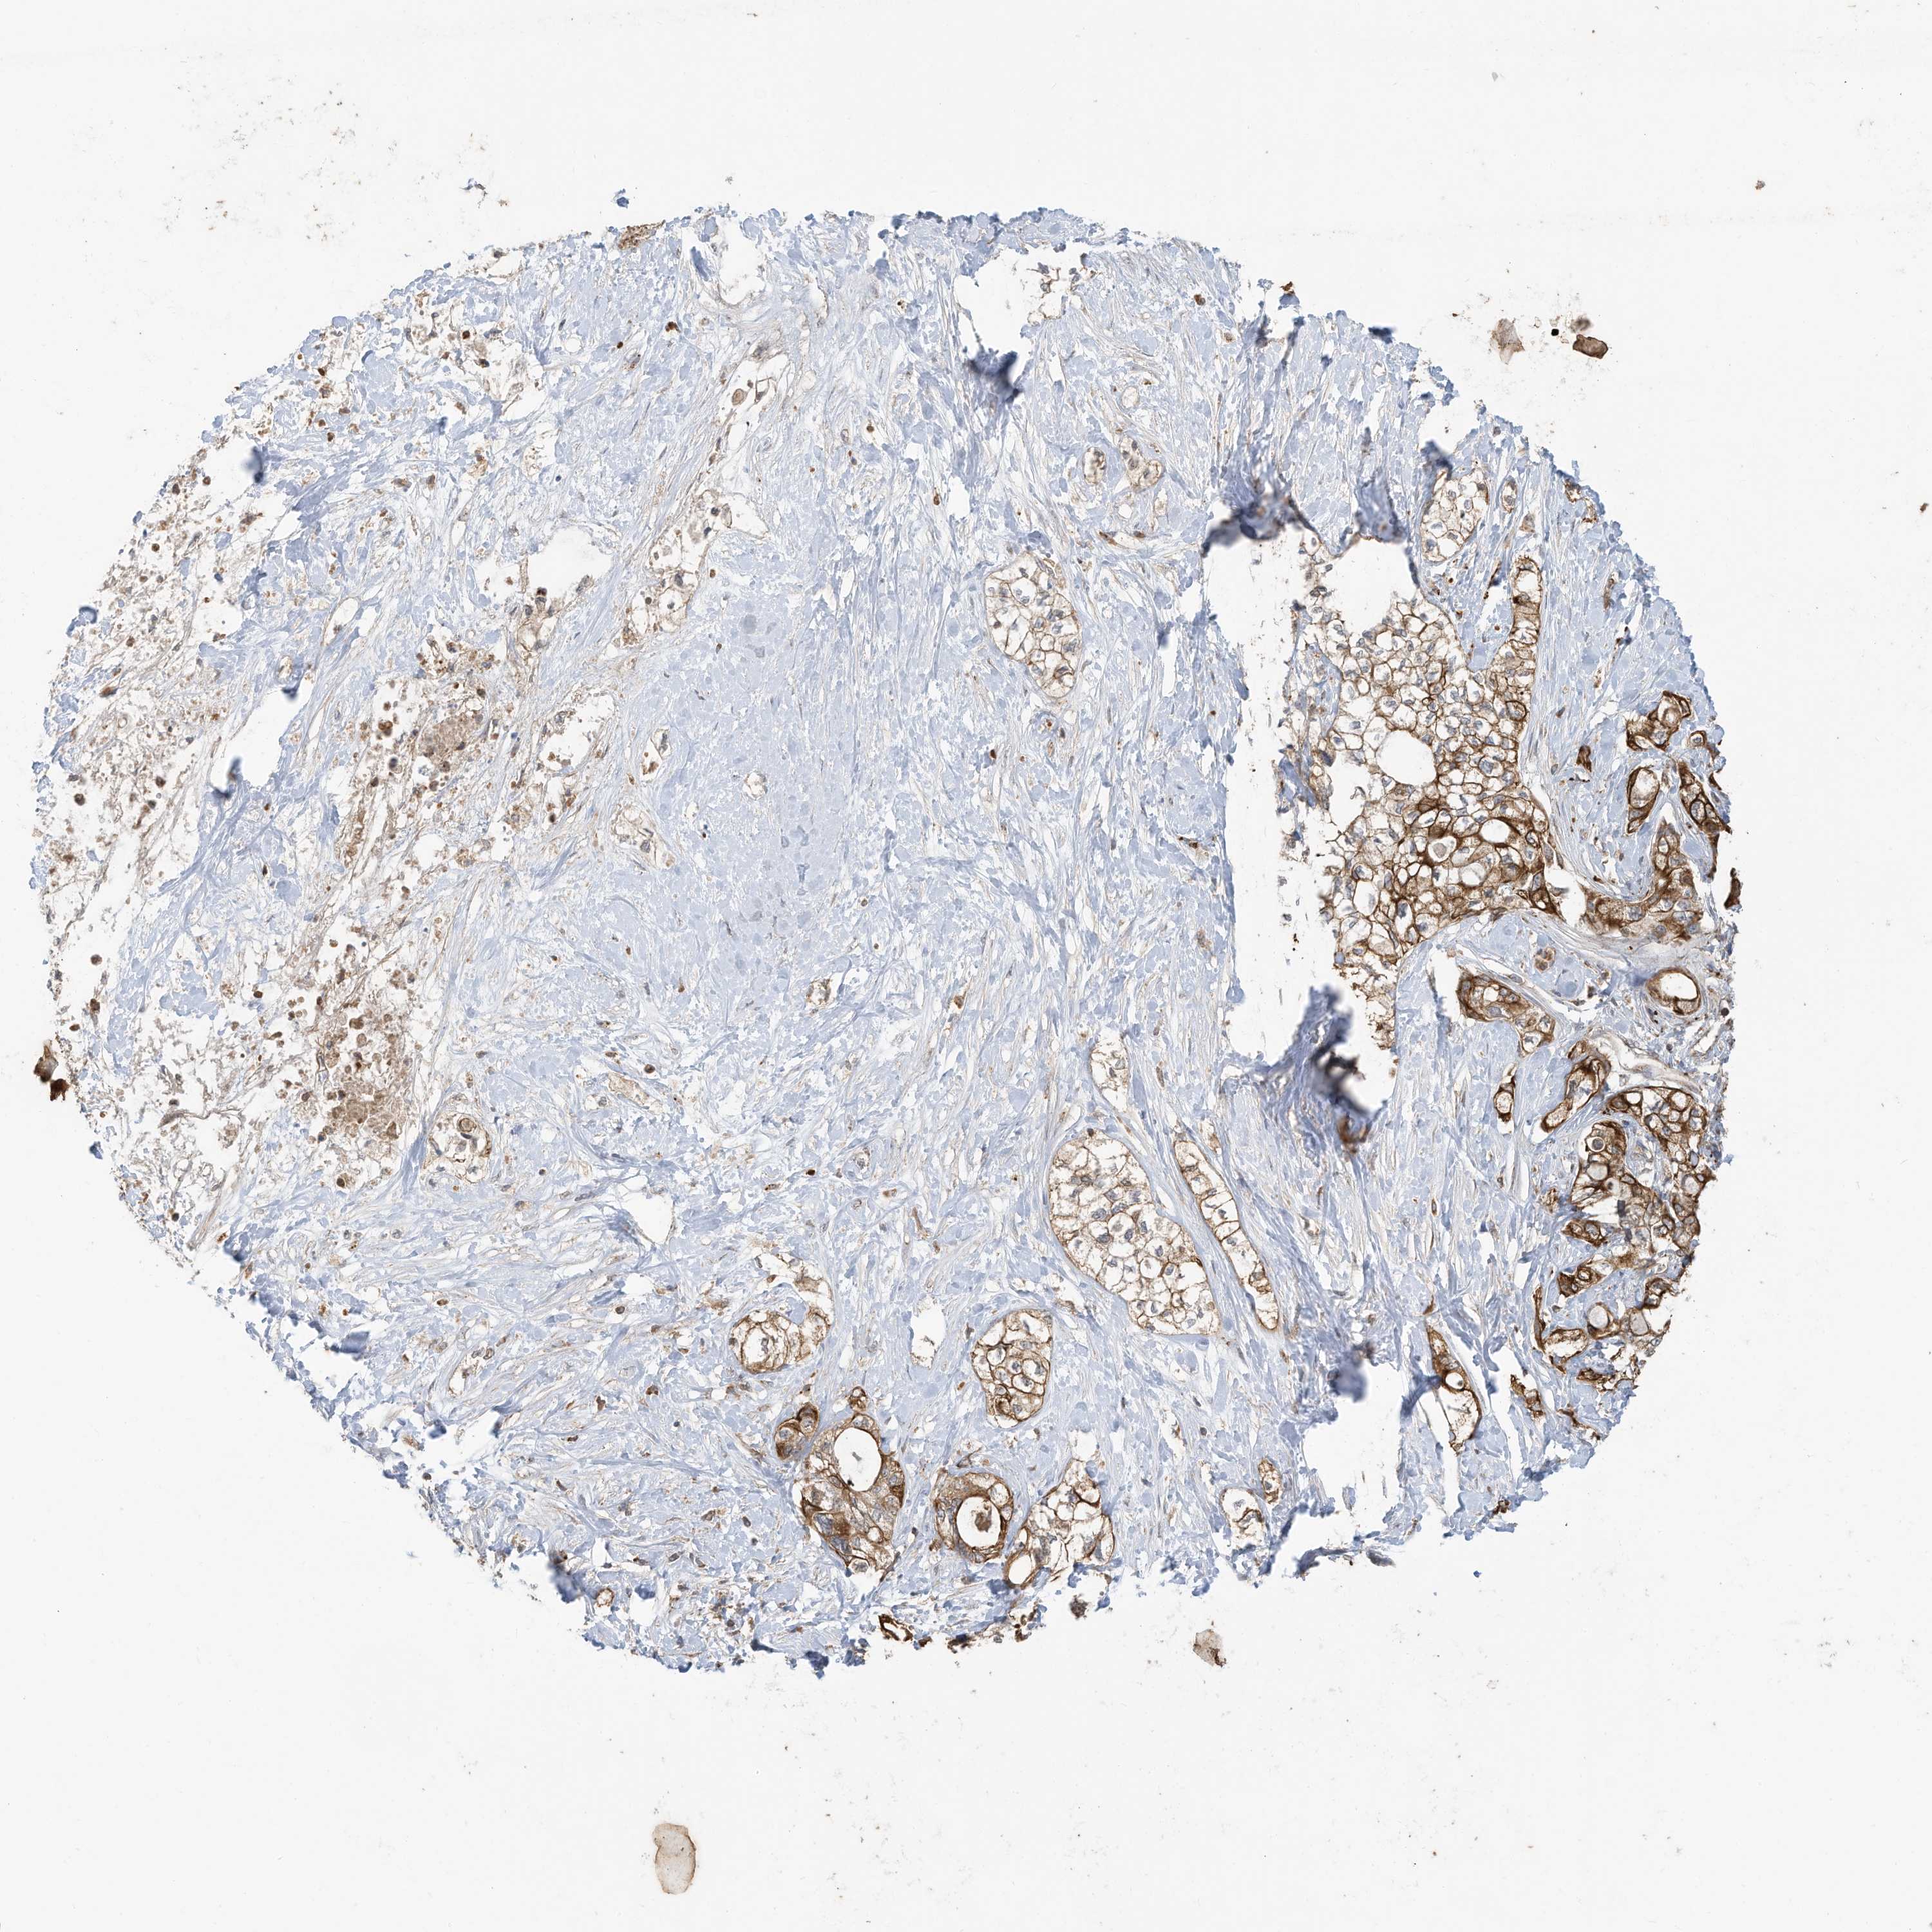

PANCREATIC CANCER - Protein expressioni

A mouse-over function shows sample information and annotation data. Click on an image to view it in a full screen mode. Samples can be filtered based on level of antibody staining by selecting one or several of the following categories: high, medium, low and not detected. The assay and annotation is described here.

Note that samples used for immunohistochemistry by the Human Protein Atlas do not correspond to samples in the TCGA dataset.

Antibody stainingi

Antibody staining in the annotated cell types in the current human tissue is reported as not detected, low, medium, or high, based on conventional immunohistochemistry profiling in selected tissues. This score is based on the combination of the staining intensity and fraction of stained cells.

Each image is clickable and will lead to virtual microscopy that enables deeper exploration of all samples and also displays staining intensity scores, fraction scores and subcellular localization as well as patient and tissue information for each sample.

Antibody HPA026826

Staining

High

Medium

Low

Not detected

Intensity

Strong

Moderate

Weak

Negative

Quantity

>75%

75%-25%

<25%

None

Location

Nuclear

Cytoplasmic/membranous

Cytoplasmic/membranous,nuclear

Adenocarcinoma, NOS